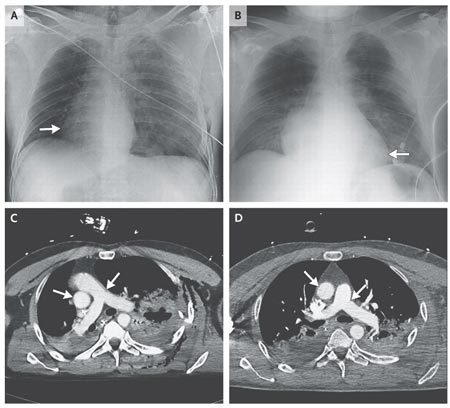

Ảnh chụp X-quang và chụp cắt lớp vi tính hé lộ, trái tim của bệnh nhân tự xoay 90 độ từ bên trái sang bên phải của lồng ngực. Ảnh: The New England Journal of Medicine |

Kết quả chụp X-quang và chụp cắt lớp vi tính (CT) lồng ngực của bệnh nhân hé lộ, trái tim của ông đã quay 90 độ sang phía bên phải.

Sau khi tháo rút hết không khí rò rỉ ở khoang ngực, trái tim của bệnh nhân đã quay sang trái. Và khoảng 24 tiếng sau đó, nó đã trở về vị trí ban đầu, bình thường ở bên trái lồng ngực ông.